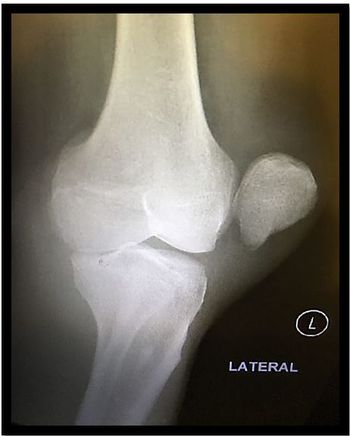

A 44-year-old man arrives at the ED via ambulance complaining of knee pain and inability to bend or fully straighten his left leg. He had been in a wrestling competition.